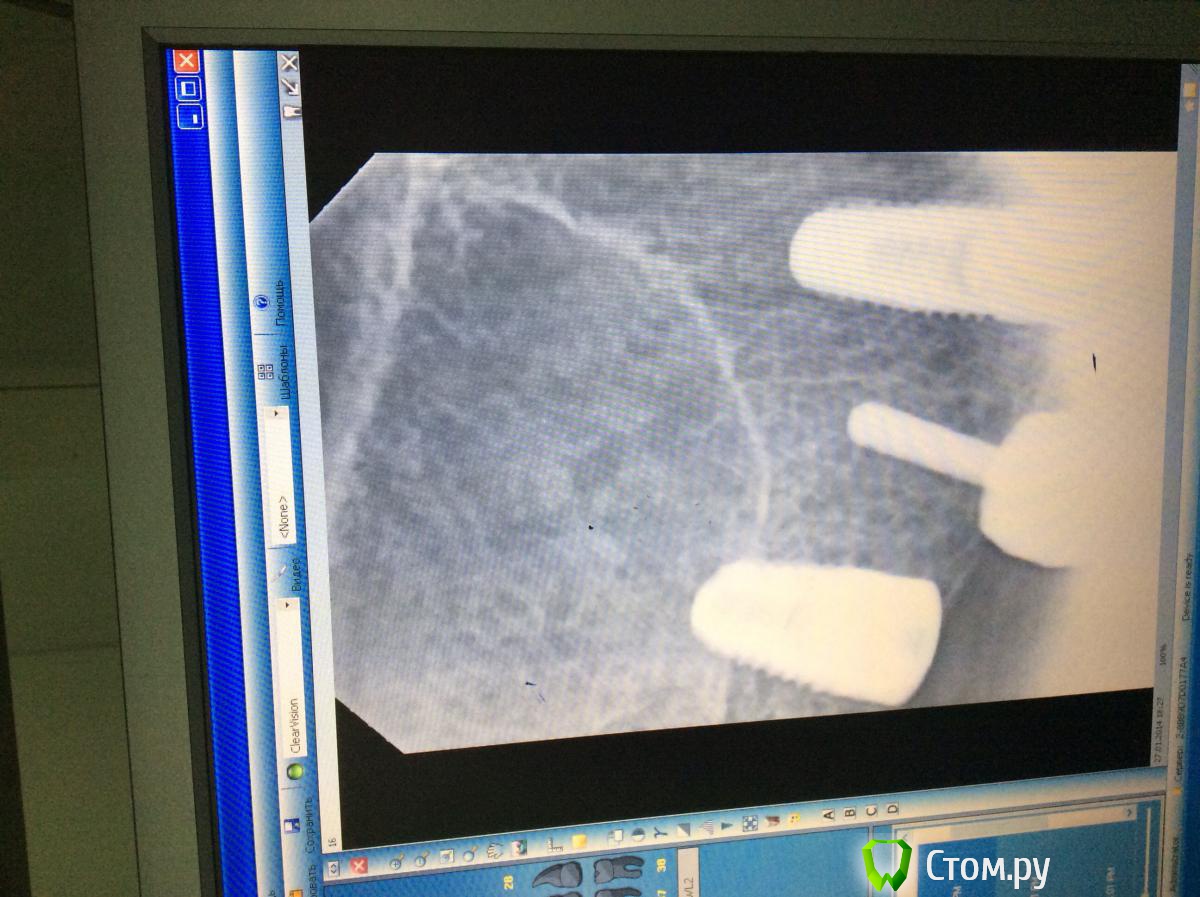

Opimar Опубликовано 27 января, 2014 Автор Поделиться Опубликовано 27 января, 2014 (изменено) Последовав вашим рекомендациям выкладываю итог работы. ОРТО и прицельные снимки. Установил: 14-3.9 на 1015-3.9 на 816-4.4 на 8 16 бикортикальная фиксация, надеюсь проблем не будет. Стабилизация была, имплантанты не болтались закручиваю всегда вручную. Теперь будем посмотреть)) Система Biotech Изменено 27 января, 2014 пользователем Opimar Ссылка на комментарий